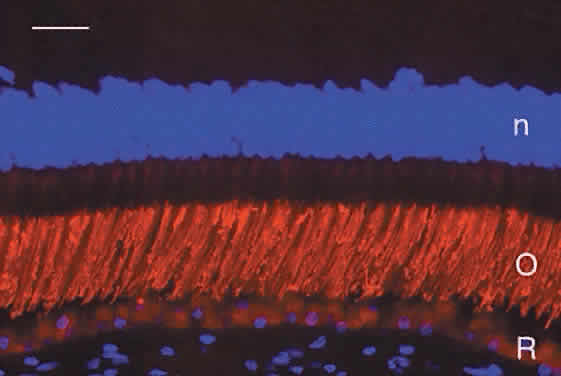

The midportion of the RPE cell contains the nucleus, cytoplasmic organelles for protein synthesis (ribosomes, rough endoplasmic reticulum, and Golgi apparatus), smooth endoplasmic reticulum, phagosomes containing outer segment tips undergoing digestion by lysosomal enzymes, and lipofuscin granules. The lipofuscin granules, which increase in number with normal aging, represent residual outer segment lipids incompletely digested by lysosomal activity. The lipofuscin granules are autofluorescent (Fig. 4A) and are relatively sparse in the RPE of children. RPE cells in older eyes are engorged with lipofuscin granules, which also contain incompletely digested melanin granules. The highest density of RPE lipofuscin is found in the macula; this high concentration of lipofuscin granules may compromise RPE functions and has been suggested to cause macular degeneration.6

Fig. 4. A. Fluorescence micrograph of adult human retina demonstrating autofluorescent lipofuscin granules that fill the retinal pigment epithelium (R) cells. Cell nuclei in the outer and inner nuclear layers (n) are counterstained blue with DAPI. C, choroid. Bar = 30 μm. B. Immunofluorescence demonstration of interphotoreceptor retinoid binding protein (*, green label) in the subretinal space of adult human retina. The retinal pigment epithelium (R) contains yellow autofluorescent lipofuscin granules. The internal limit of the subretinal space is the external limiting membrane (E). Bar = 20 μm. C. Demonstration of cone matrix sheaths (*, labeled red with peanut agglutinin lectin) that surround individual cone outer segments in the subretinal space. Lipofuscin in retinal pigment epithelium (R) contains yellow-gold autofluorescent lipofuscin granules. C, choroid. Nuclei in the outer and inner nuclear layers (n) are counterstained blue with DAPI. Bar = 20 μm.